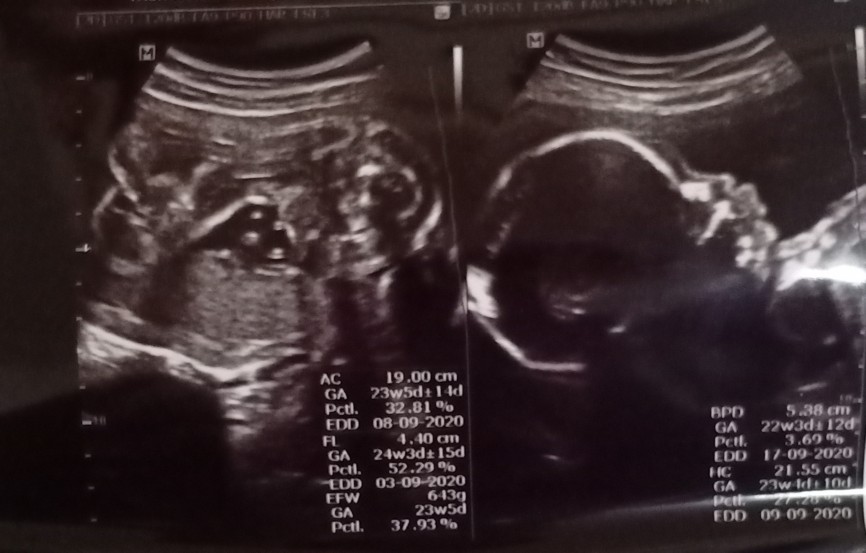

ขอดู รูปซาว หน่อยค่ะว่าเหมื่อนกันไหม หมอ บอกว่า เป็น ญ เพราะไม่มีจู๋โผลมา บ้านอื่น ได้ ญ แบบนี้หรือเปล่าค่ะ แม่แอบกังวล อยากได้ญ กลัว จู่ โผล่มาทีหลัง 😁23+4.

บ้านนี้คุณหมอว่าเป็นผู้หญิงตั้งแต่24สัปดาห์